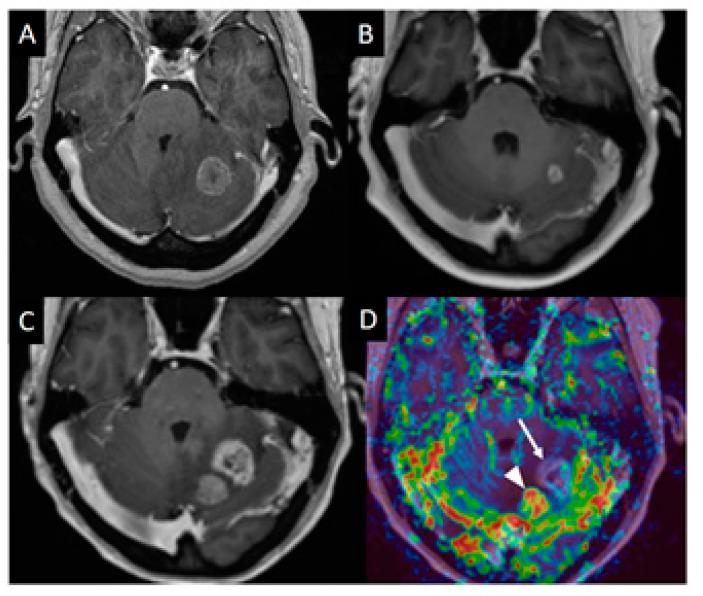

Onboard, real-time, imaging techniques, from the original megavoltage planar imaging devices, to the emerging combined MRI-Linear Accelerators, have brought a huge transformation in the ability to deliver targeted radiation therapies. Each generation of these technologies enables lethal doses of radiation to be delivered to target volumes with progressively more accuracy and thus allows shrinking of necessary geometric margins, leading to reduced toxicities. Alongside these improvements in treatment delivery, advances in medical imaging, e.g., PET, and MRI, have also allowed target volumes themselves to be better defined. The development of functional and molecular imaging is now driving a conceptually larger step transformation to both better understand the cancer target and disease to be treated, as well as how tumors respond to treatment. A biological description of the tumor microenvironment is now accepted as an essential component of how to personalize and adapt treatment. This applies not only to radiation oncology but extends widely in cancer management from surgical oncology planning and interventional radiology, to evaluation of targeted drug delivery efficacy in medical oncology/immunotherapy. Here, we will discuss the role and requirements of functional and metabolic imaging techniques in the context of brain tumors and metastases to reliably provide multi-parametric imaging biomarkers of the tumor microenvironment.